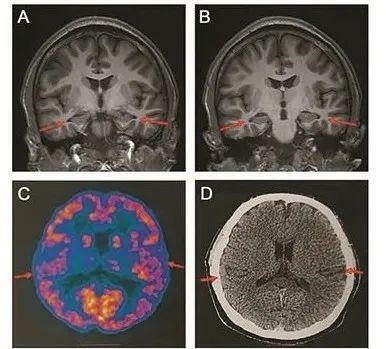

醫院為患者做了多種檢查,包括當前用於診斷阿爾茲海默症的最權威手段——腦脊液指標檢測和PET掃描,患者還接受了多種量表測試。掃描影像等顯示,患者存在輕度的腦萎縮等症狀,部分腦脊液指標也存在異常,最終患者被臨床診斷為阿爾茲海默症患者。